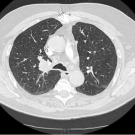

A Rare Case Report on Radiation Recall Pneumonitis in a Patient Treated with Durvalumab for Non-Small Cell Lung Cancer

Syed M. Imam, DO; Faryal Haider, MD; Syed A.A. Rizvi, PhD, MBA

A 77-year-old man first presented to the emergency department (ED) due to hemoptysis and intermittent shortness of breath.